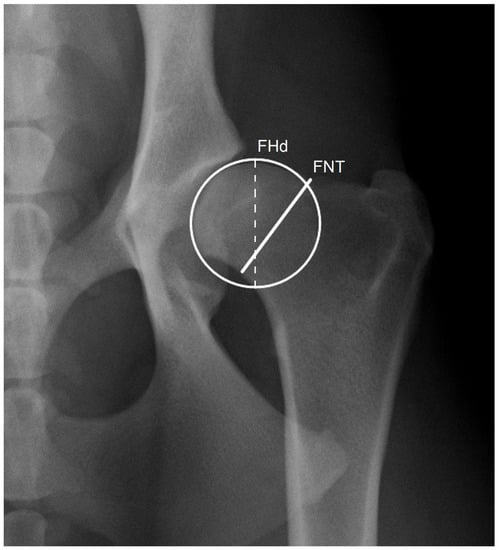

The minimal FNT was measured by drawing a straight line, roughly perpendicular to the anatomical axis of the femoral neck, connecting the two closest points between the proximal and distal margins of the femoral neck in a VDHE view. The femoral head diameter was determined as a diameter of a circle outlining the margin of the femoral head (Figure 1). These measurements were performed by examiner 1 (E1) in two independent sessions (S1 and S2) to evaluate repeatability and by examiner 2 (E2) to test the reproducibility using specific DICOM viewer and editor software (Dys4Vet version 2.0, accessed between 1 October and 31 December 2022). The FNTi was determined by dividing the FNT by the femoral head diameter.

Figure 1. Detail of the left hip joint of a dog showing a circle delimiting the head of the femur with 31.5 mm diameter (FHd; dashed line) and a line joining the proximal and distal borders of the femoral neck to determine its thickness of 28.7 mm (FNT), corresponding to an index (FNTi) of 0.91.